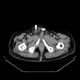

Inguinal bladder hernia

An inguinal hernia is a protrusion of abdominal-cavity contents through the inguinal canal. Symptoms are present in about 66% of affected people. [Source: Wikipedia ]